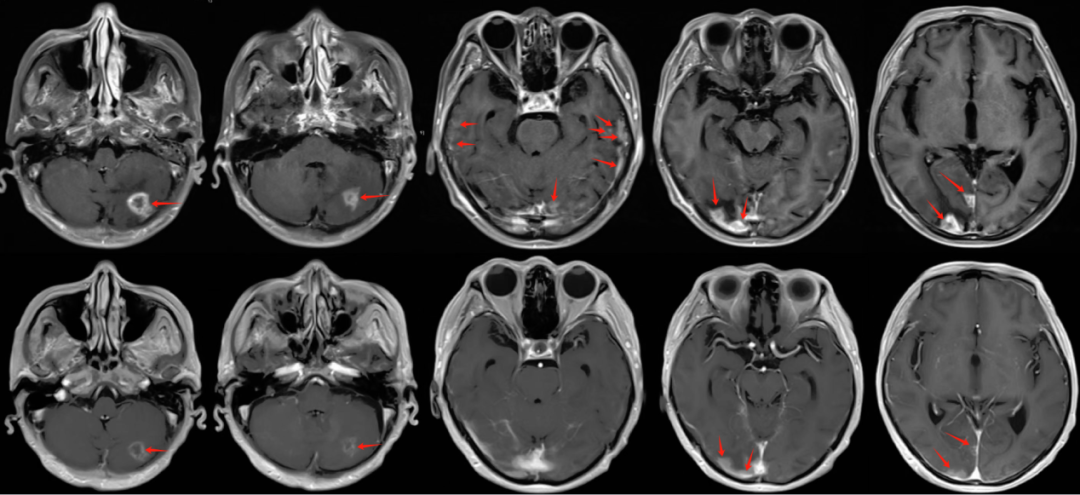

患者入院后磁共振檢查可見,左側(cè)小腦半球,雙側(cè)顳葉、雙側(cè)枕葉多發(fā)轉(zhuǎn)移病灶及轉(zhuǎn)移結(jié)節(jié);病灶區(qū)大片腦組織水腫。

圖注:磁共振檢查,上排為T1增強(qiáng)像,可見患者左側(cè)小腦半球,雙側(cè)顳葉、雙側(cè)枕葉多發(fā)明顯強(qiáng)化的轉(zhuǎn)移病灶及轉(zhuǎn)移結(jié)節(jié);下排為FLARE像,可見病灶區(qū)大片腦組織水腫。